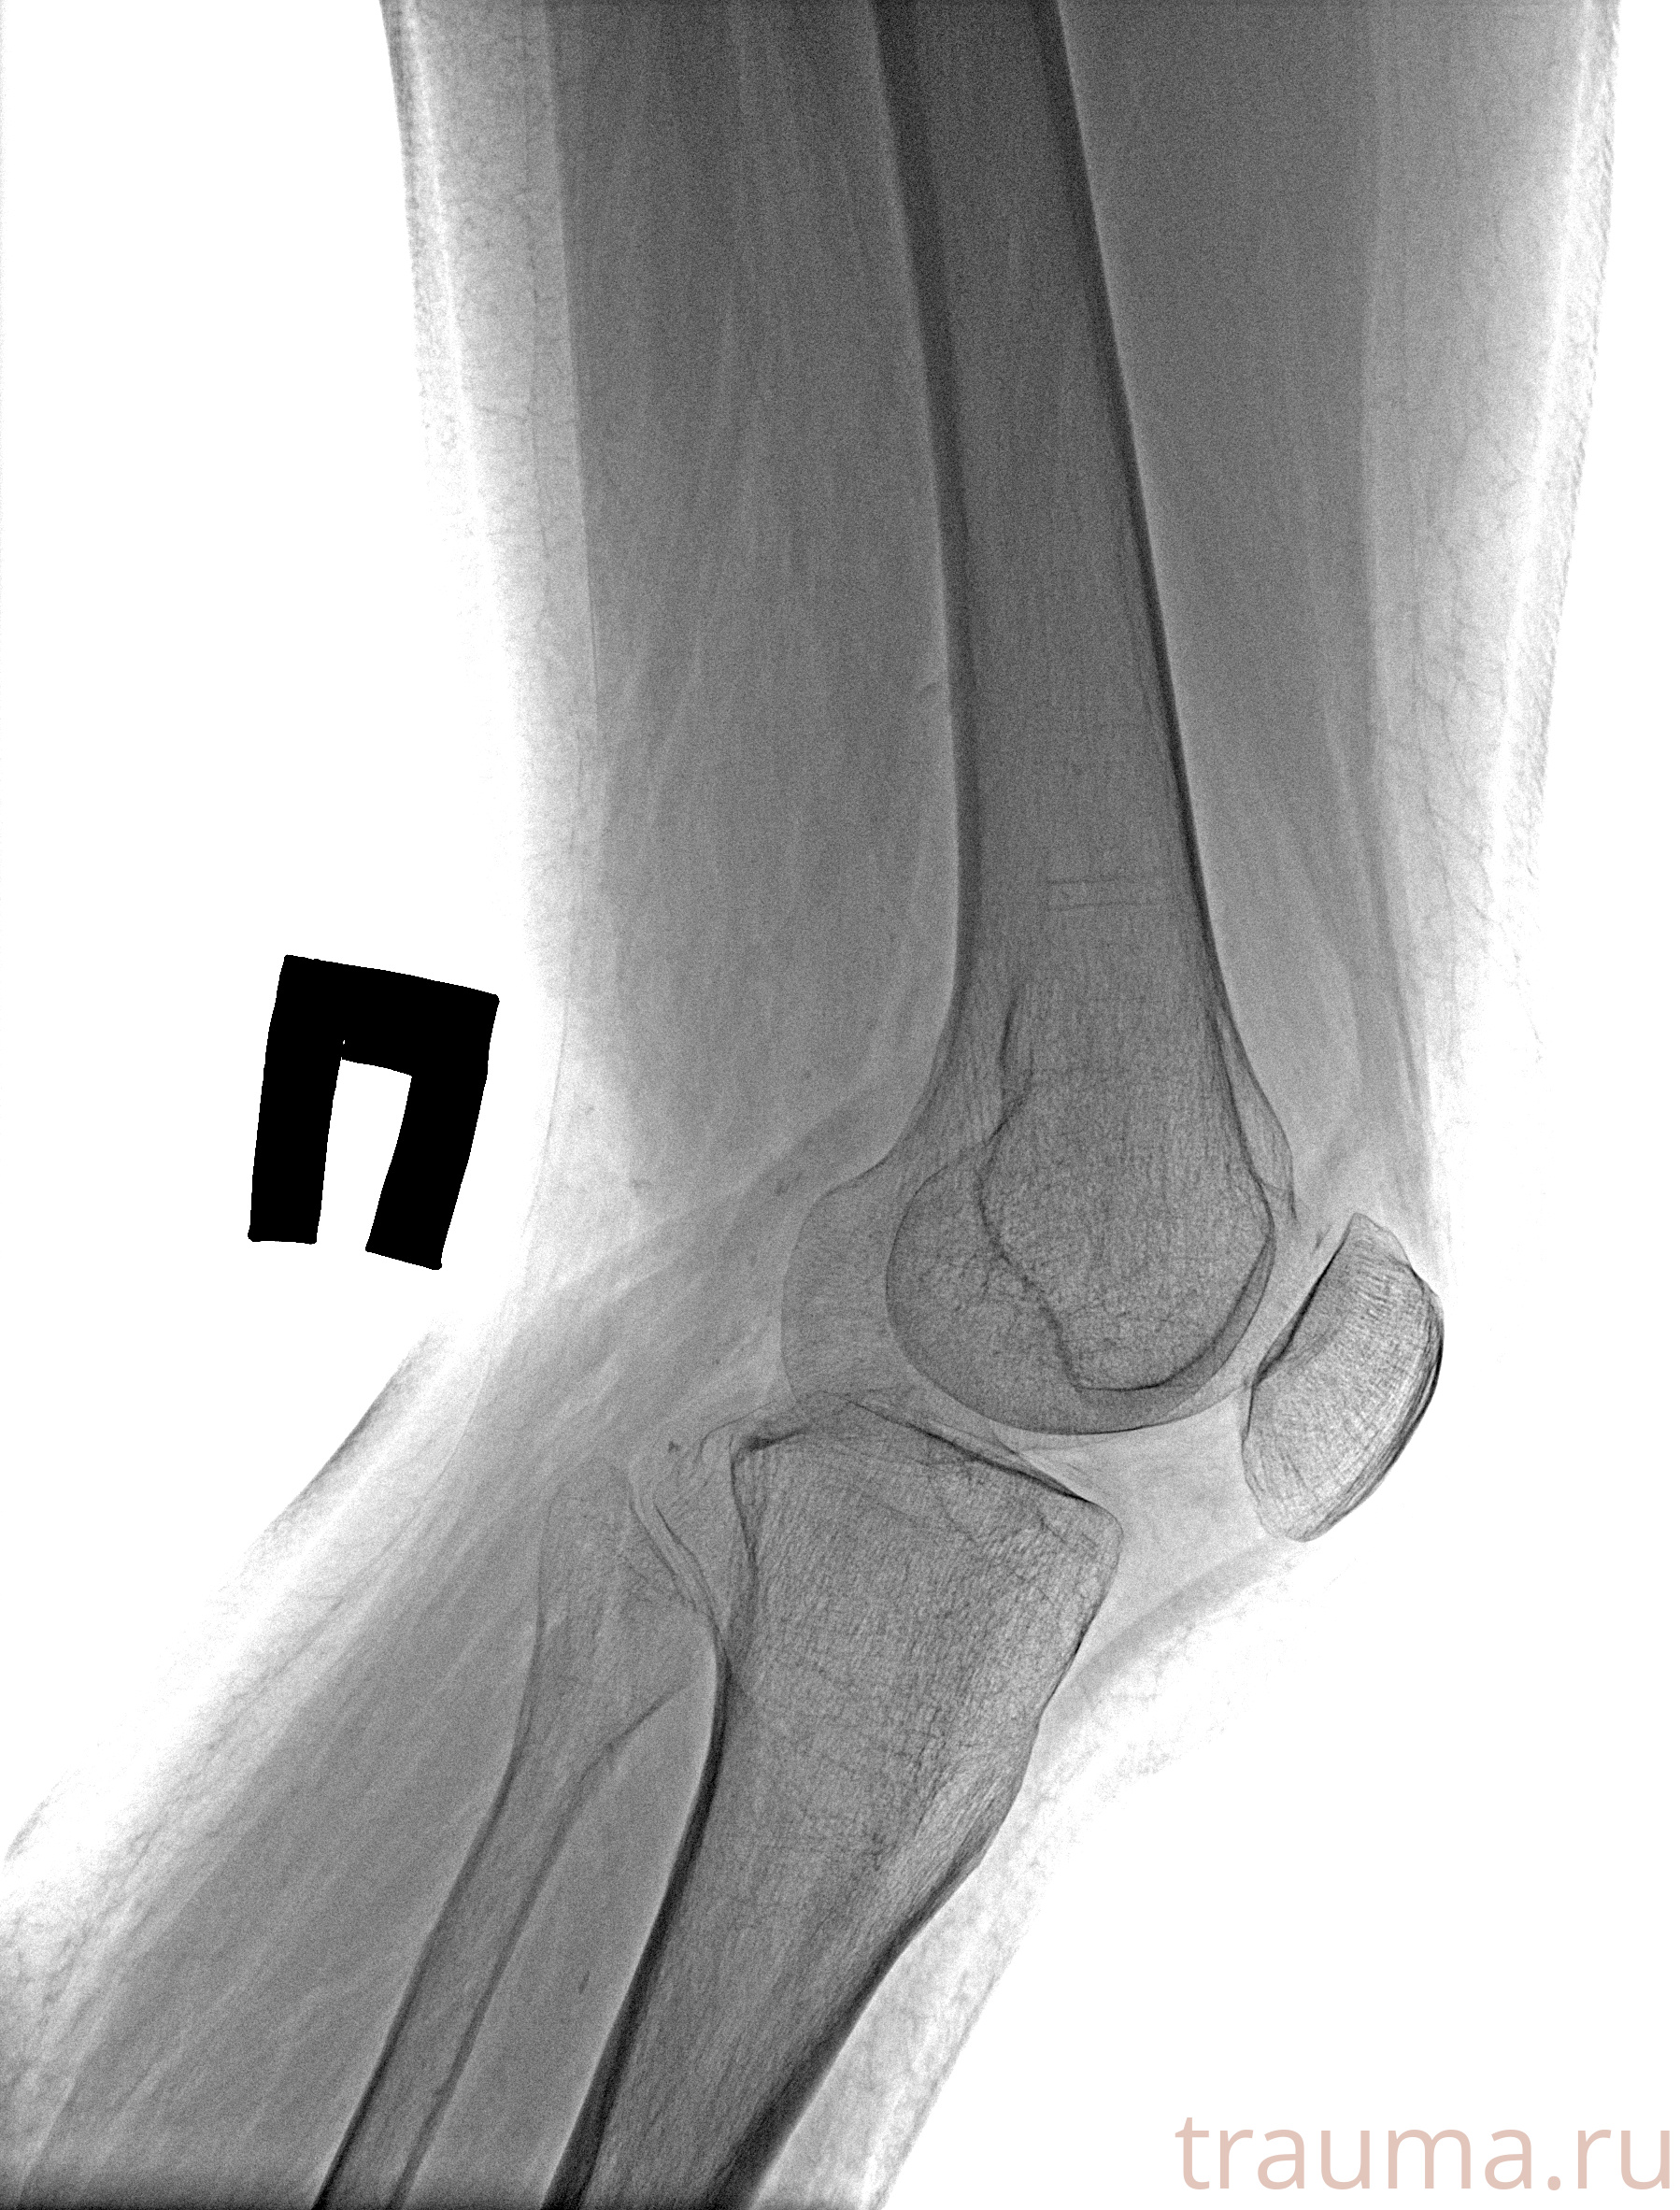

Рентгенограммы

Рентген на дому: по вашему адресу приезжает врач-рентгенолог, травматолог-ортопед с мобильным рентгеновским аппаратом, проводит диагностику травмы или заболевания, делает необходимые рентгенограммы, дает рекомендации по дальнейшему лечению. Получить качественные снимки в домашних условиях возможно благодаря уникальной методике, разработанной МосРентген Центром для института  Склифосовского